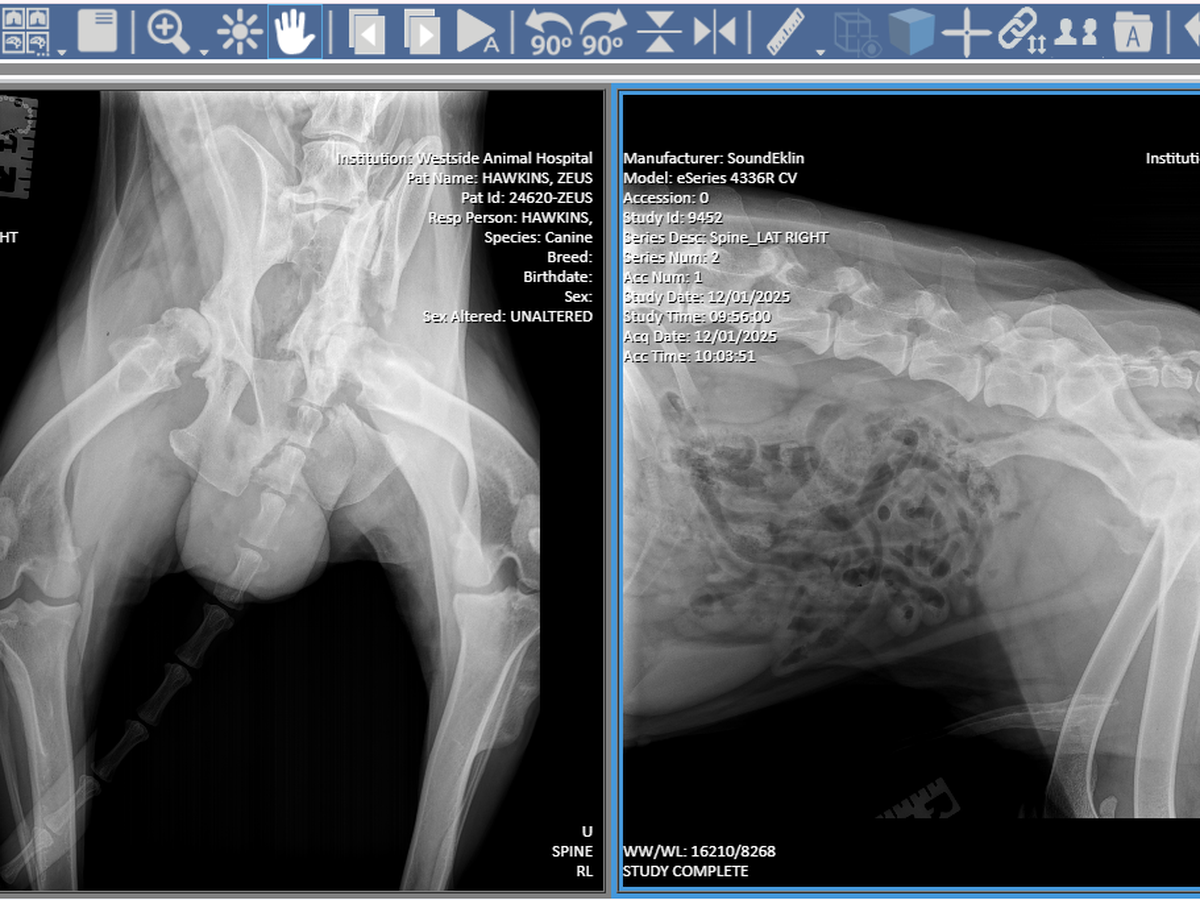

Because Zeus did not receive immediate medical care, his injuries worsened over time. He suffered a broken pelvis, which led to severe muscle atrophy in his left leg, leaving him in significant pain and unable to properly use it. Despite everything he has endured, Zeus continues to fight with incredible strength and resilience.

At this time, Zeus is being medically managed and closely monitored while awaiting an orthopedic surgical evaluation to determine the best course of treatment. He is currently prescribed Gabapentin, Carprofen, and Trazodone to help control pain, inflammation, and to keep him safely sedated in order to prevent further injury or additional damage while we await definitive surgical care.

There is a possibility that Zeus may need to undergo left leg amputation in order to relieve pain and give him the best chance at a comfortable, mobile life. The minimum cost of care is estimated at $8,000, and it may increase depending on the surgical treatment required, post-operative care, rehabilitation, and follow-up visits.